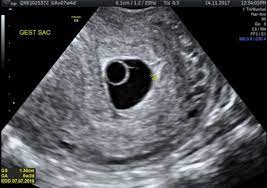

Nov 10, 2020 · how long can you carry a blighted ovum? What to do with a blighted ovum pregnancy? A blighted ovum will cause a miscarriage usually at 7 to 12 weeks of pregnancy. You have a placenta and a gestational sac, but the embryo doesn't grow. How long can a blighted ovum pregnancy last?

Can a blighted ovum cause an early miscarriage? Nov 10, 2020 · how long can you carry a blighted ovum? Many women need support and time to grieve. It's also called anembryonic pregnancy or empty sac. What to do with a blighted ovum pregnancy? The placenta and sac still give off pregnancy hormones. Dec 13, 2017 · the sonogram will show the placenta and empty embryonic sac. While you can technically get pregnant again as soon as your periods return, we recommend that you wait for about three months to fully heal after a miscarriage.

Dec 13, 2017 · the sonogram will show the placenta and empty embryonic sac. While a blighted ovum leads to loss of pregnancy, most women tend to have healthy pregnancies and babies subsequently. What are the treatment options? Nov 10, 2020 · how long can you carry a blighted ovum? While you can technically get pregnant again as soon as your periods return, we recommend that you wait for about three months to fully heal after a miscarriage. A miscarriage is when a pregnancy ends on its own within the first 20 weeks. How long can a blighted ovum pregnancy last? These cause a pregnancy test to show positive, and can give you symptoms of pregnancy. You have a placenta and a gestational sac, but the embryo doesn't grow. Your body understands the pregnancy is not developing properly and starts to shed blood and tissue from the uterus. It's also called anembryonic pregnancy or empty sac. Blighted ovum is a type of early pregnancy loss. Experiencing a miscarriage for any reason is painful.